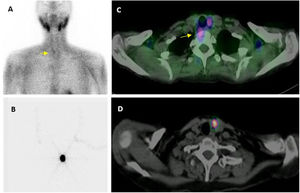

Imagen preoperatoria. Localización con MIBI: adquisición planar (A) en que se intuye un pequeño adenoma inferior derecho (flecha), que la imagen de fusión SPECT/TC (C) confirma y localiza en situación ectópica, prevertebral derecha.

Localización preoperatoria de adenoma paratiroideo inferior izquierdo mediante técnica ROLL: imágenes planar (B) y transaxial de SPECT/TC (D), tras la administración intralesional de MAA.

Se realiza también gammagrafía SPECT/TC para confirmar la correcta inoculación en el adenoma, es decir, la localización intralesional (concéntrica) de la actividad y la ausencia de dispersión o de contaminación, así como para realizar la correspondiente marca cutánea (fig. 2).